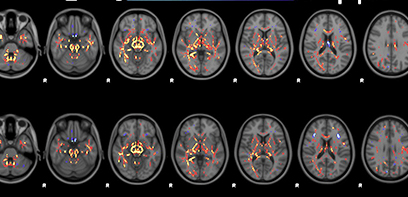

Media Release: MRI technique shows unique signatures of concussion

The research team used a technique that combined multiple brain imaging measures to be able to look at structural and functional information at the same time. The result was a much more sensitive and complete picture of concussion injury.